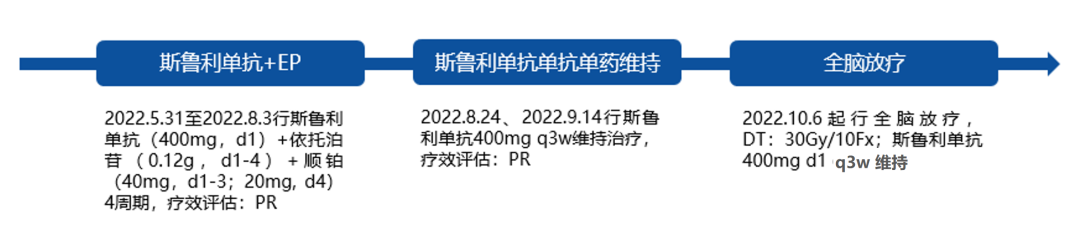

斯鲁利单抗优例共赏丨一例合并多发肝转移小细胞肺癌患者免疫治疗...

斯鲁利单抗优例共赏丨一例合并多发肝转移小细胞肺癌患者免疫治疗...